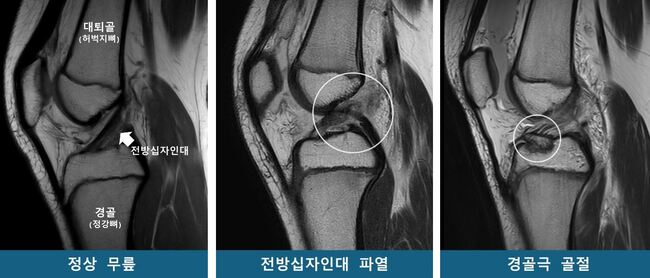

운동 중 무릎을 다친 소아청소년 중 일부는 십자인대가 끊어지고, 일부는 무릎뼈(정강뼈의 상부, 경골극)가 골절된다. 이런 차이가 ‘타고난 무릎 모양’ 때문에 발생한다는 연구 결과가 나왔다. 대퇴과간 절흔 폭(대퇴골과 정강뼈 사이의 공간)이 좁으면 전방십자인대 파열 위험이 높아지고, 경골(정강뼈) 바깥쪽 관절면의 가파른 경사는 전방십자인대 파열과 경골극 골절 모두에 영향을 미친다는 사실이 규명됐다. 이 결과는 무릎 부상 위험이 높은 소아청소년을 선별하고, 개인별 맞춤치료 지침을 마련하는 근거가 될 것으로 기대된다.

소아청소년은 뼈와 근육 발달이 미성숙해 스포츠 손상에 취약하다. 특히 ‘전방십자인대 파열’과 ‘경골극 골절’은 소아청소년에게 발생하기 쉬운 대표적인 무릎 손상이다. 같은 외상을 입어도 어떤 환자는 십자인대가 파열되고, 다른 환자는 경골극 골절이 발생하는데, 이처럼 서로 다른 손상이 발생하는 원인은 명확치 않다.

연구팀은 소아청소년을 53명씩 △전방십자인대 파열군 △경골극 골절군 △대조군(정상 무릎)으로 구분하고 연령·성별을 매칭했다. 이후 자기공명영상(MRI)을 재구성한 3차원 영상을 바탕으로 14개의 해부학적 지표를 분석했다.

그 결과, 두 가지 무릎 손상군은 대조군보다 ‘경골 바깥쪽 관절면 경사’가 유의미하게 높았다. 통계 분석에 따르면 경사가 높을수록 전방십자인대 파열 및 경골극 골절 발생 위험이 각각 1.42배, 1.33배 증가해, 이 값이 소아청소년의 주요 무릎 손상에 대한 위험인자로 확인됐다.

반면 대퇴과간 절흔 폭(무릎뼈 사이 공간)은 전방십자인대 파열군에서만 유의미한 연관성이 있었다. 특히 이 폭이 넓을수록 파열 위험이 감소하는 보호 효과가 확인됐다.

연구팀은 경골 바깥쪽 관절면의 경사가 가파를수록 무릎에 무게가 실릴 때 대퇴골(허벅지뼈)이 바깥쪽으로 회전하며, 그 결과 전방십자인대가 과부하되어 파열이나 경골극 골절로 이어질 수 있다고 설명했다. 또한 대퇴과간 절흔 폭이 넓을 경우, 전방십자인대가 대퇴골과 덜 충돌하기 때문에 파열 위험이 낮아지는 경향이 있다고 밝혔다.